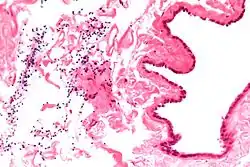

Micrograph of a spermatocele. The characteristic sperm are present (black dots - left of image). H&E stain.

Dilated rete testis containing spermatozoa within cyst lumen. H&E stain 20x